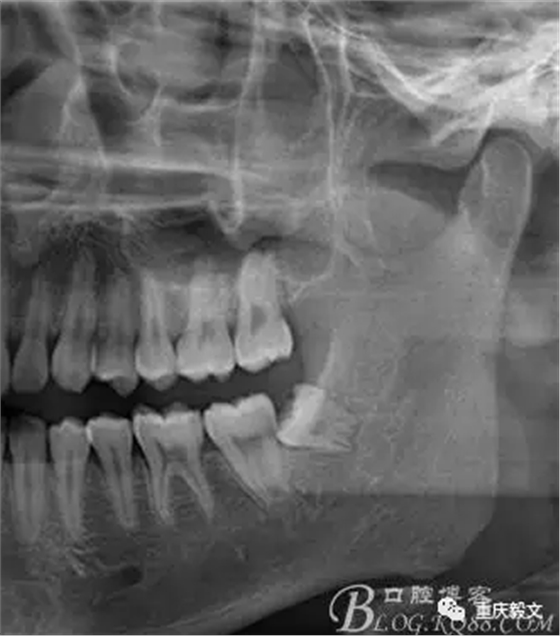

圖1術(shù)前的影像檢查 : x線(xiàn)檢查的目的:檢查有無(wú)智齒的存在。如有阻生智齒存在,確定是部分骨阻生還是完全骨阻生。檢查阻生智齒的類(lèi)型,是近中位、垂直位或水平位等。檢查阻生智齒的大小和牙根的長(zhǎng)短、數(shù)目、形態(tài)等;有無(wú)牙根彎曲和彎曲方向與程度;牙根有無(wú)肥大、是否與周?chē)琴|(zhì)粘連。.檢查阻生智齒與第二磨牙的關(guān)系.檢查阻生智齒與下頜管的關(guān)系及距離.